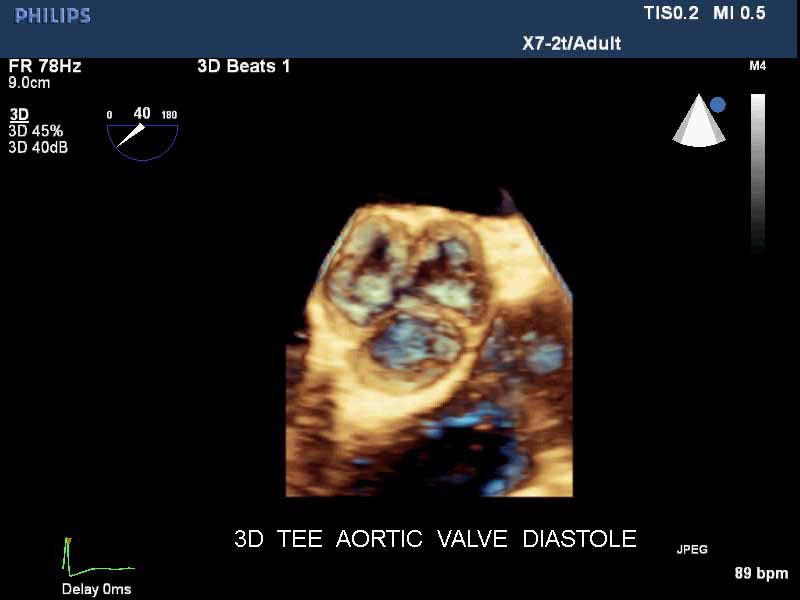

• Live 3D TEE: Эта функция позволяет проводить чреспищеводную эхокардиографию в режиме реального времени, что позволяет оценить механические сокращения сердца с точностью, необходимой для оценки результатов хирургического вмешательства.

• Чреспищеводный УЗИ датчик Philips Х7-2T